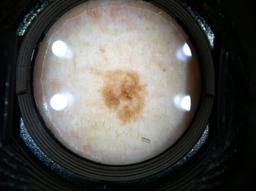

Biopsy-confirmed melanocytic and non-melanocytic skin lesions. This dataset includes over 500 melanomas. Many images have polarized and contact variants.